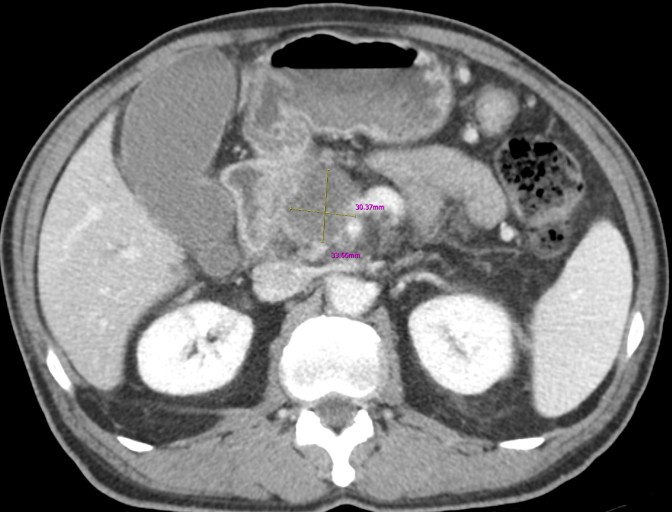

췌장암 조기 진단을 위한 간략한 주의사항

- 복합적인 증상 주의: 단순 소화 불량이 아닌, 복부 통증 + 체중 감소 + 황달 + 새로운 당뇨병 등 여러 증상이 복합적으로 나타나면 즉시 병원을 찾아 정밀 검사(복부 CT, MRI, 내시경 초음파 등)를 받아야 합니다.